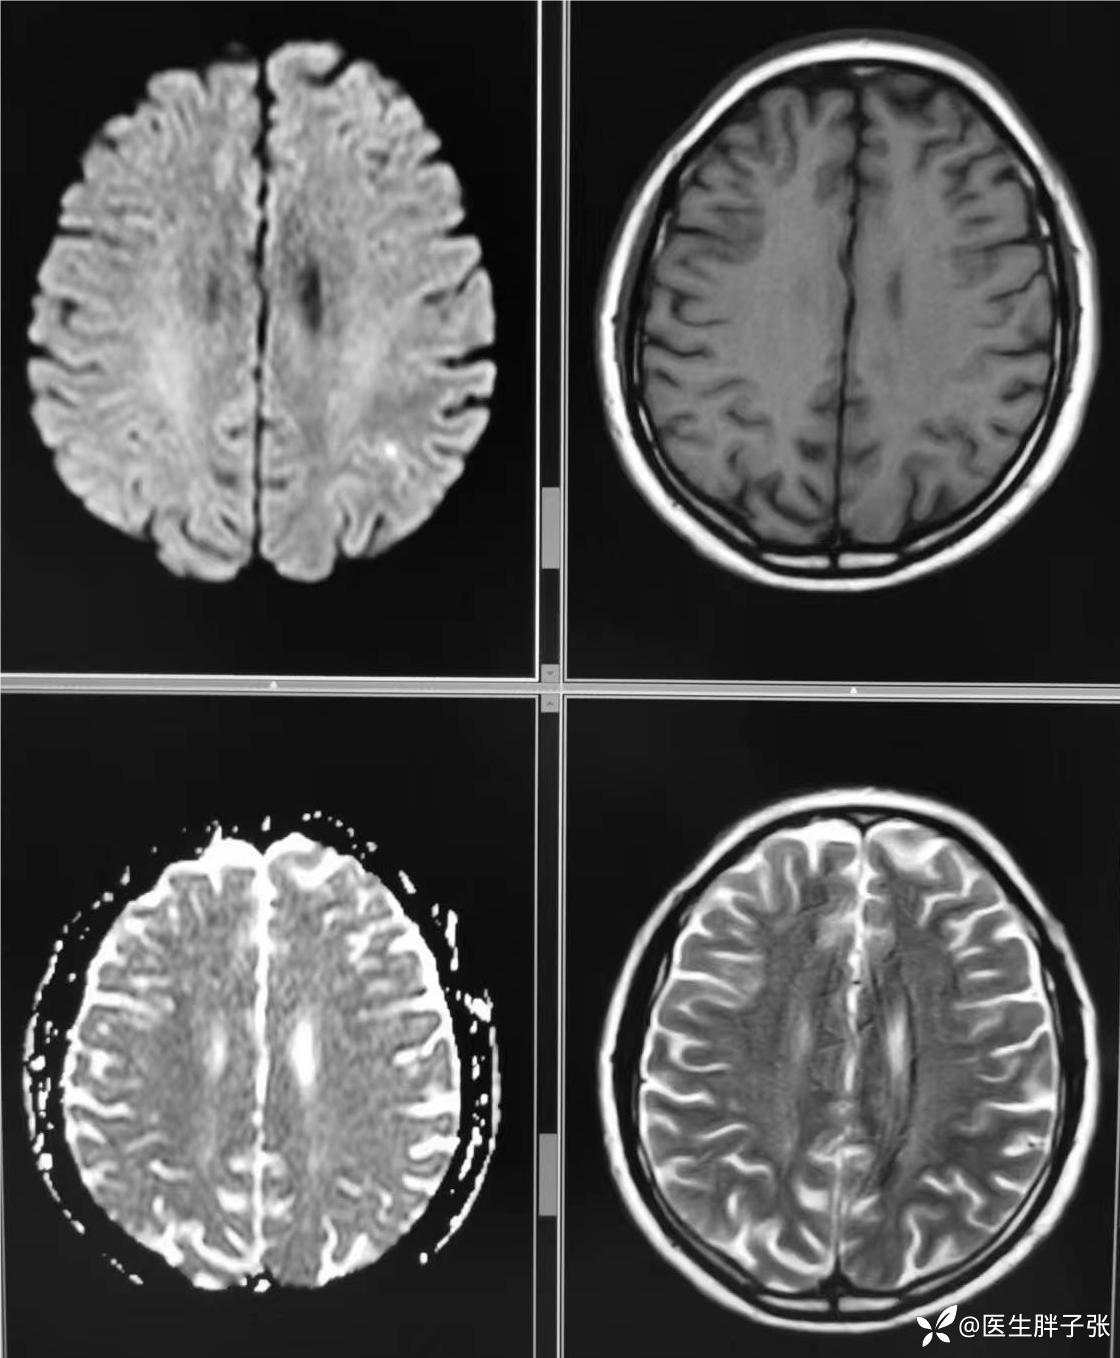

颅脑MR回报左侧顶叶新近梗死灶;多发腔隙性脑梗死及缺血灶;MRA未见异常。

再次查看核磁,考虑患者左侧顶枕叶及右侧枕叶脑组织存在混杂信号。

结合患者应用甘露醇后症状缓解,值班医生认为存在静脉窦血栓可能。